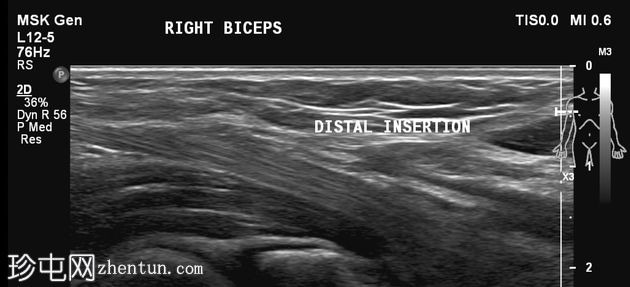

肘关节屈曲及肌肉收缩动态成像:肱二头肌短头和长头肌纤维之间出现充满液体的裂隙,提示局部肌筋膜分离/拉伤。未见肌纤维全层撕裂。肱二头肌远端止点正常。